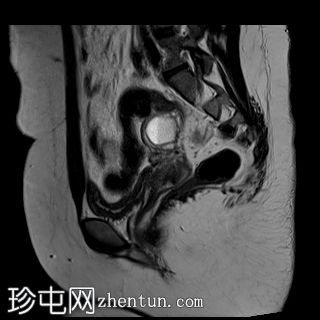

矢状位

T2加权像

双侧卵巢位置接近(卵巢相吻),左侧卵巢内可见一边界清晰的囊性病变,大小约3.1 × 2.7 × 2.9 cm,T1加权像呈高信号,T2加权像可见暗点征及内部暗点征。以上MRI特征符合卵巢子宫内膜异位囊肿的诊断。

右侧卵巢可见一囊肿,大小约为 2.8 × 2.0 × 2.2 cm,T1 加权像呈高信号,囊内可见液-液平面,提示囊内含有不同时期的出血性物质。由于对侧卵巢存在典型的子宫内膜异位囊肿,且该囊肿无强化,影像学表现强烈提示为另一子宫内膜异位囊肿。

子宫大小、轮廓及信号强度均正常,子宫内膜分区结构完整。未见局灶性肌层病变,子宫内膜厚度在正常范围内。

左侧盆腔可见少量游离液体。